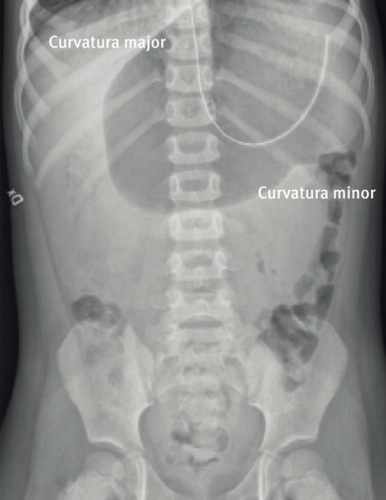

Buköversikt visar en distenderad ventrikel liggande i det vertikala planet (mesenteroaxial) (Figur 2) eller i det horisontella planet (organoaxial) (Figur 3). En kraftigt dilaterad ventrikel kan försvåra diagnosen, eftersom det kan vara svårt att definiera ventrikelns olika delar. Avlastning med ventrikelsond och därefter övre passageröntgen ger diagnosen.

Vid mesenteroaxial volvulus är ventrikeln uppochnervänd, med pylorus ovanför den gastroesofageala övergången (kardia) (Figur 4). Vid organoaxial volvulus är ventrikeln liggande i horisontalplanet, med curvatura major ovanför curvatura minor (Figur 5).